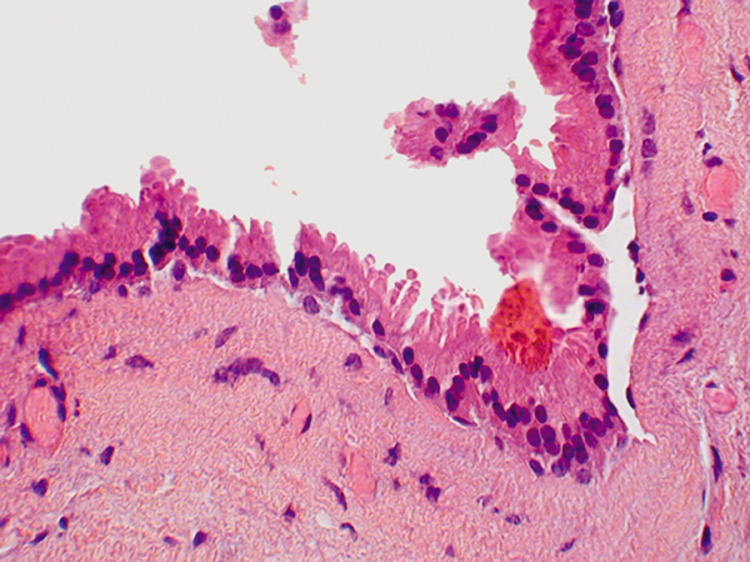

TUMORS Epithelial Tumors The epithelial lining of the lacrimal sac is the same as the rest of the upper respiratory tract (i.e., pseudostratified columnar epithelium). Therefore, tumors are similar to those found elsewhere in the upper respiratory tract, namely papillomas, squamous cell carcinomas, transitional cell carcinomas, and adenocarcinomas. Tumors of the lacrimal sac, however, are relatively rare. They generally cause early symptoms of epiphora, and, upon irrigation, blood may reflux from the punctum. Overlying skin ulceration or telangiectasias may also be associated with lacrimal sac tumors. Papillomas may be squamous, transitional, or adenomatous (Fig. 54). Rarely, a lacrimal sac papilloma may undergo oncocytic metaplasia (i.e., an eosinophilic cystadenoma or oncocytoma). The histology of squamous cell carcinomas is identical to that of those found elsewhere, and these carcinomas are the most common (Fig. 55). Transitional cell carcinomas are composed of transitional cell epithelium showing greater or lesser degrees of differentiation (Fig. 56). Adenocarcinomas are composed of malignant glandular elements. Melanocytic Melanocytic tumors arising from the lacrimal sac are quite rare and are identical histologically to those found in the lid. Mesenchymal The same mesenchymal tumors that involve the lids and orbit may involve the lacrimal sac. |